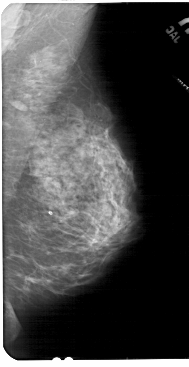

A_1842_1.LEFT_MLO

LEFT_MLO LINES 5491 PIXELS_PER_LINE 3121 BITS_PER_PIXEL 12 RESOLUTION 43.5 OVERLAY